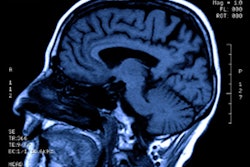

In comparing the two MRI scans, the researchers visually noticed areas of T1 hypointense and T2 hyperintense foci of encephalomalacia in the midbrain of the brainstem, which is consistent with atrophy. In addition, total gray-matter volume decreased by 14% over that time. The largest volume shrinkage was in the ventral diencephalon (-10.3%), followed by the frontal lobes (-3.6%) and the brainstem (-2.7%).

"The reason [volume loss] happens in the midbrain is because the force of football impacts are triangulated into that region," Raji explained. "The frontal lobes are affected because they are literally right behind the skull when the person is hitting their head. The ventral diencephalon sits on top of the brainstem, so it also makes sense that that region of the brain is affected as well."

Increased FDDNP signal in the midbrain on brain PET (A) of an NFL player with suspected CTE. The image correlates to midbrain volume loss in the case study by Raji et al (B) from the four-year follow-up MRI of the study subject. (Image A adapted from Barrio et al., 2015.) Images courtesy of UCLA Health.

Interestingly, the MRI scans revealed the volume of the hippocampus increased by 5.2% over four years. There also was no volume loss in the temporal or parietal lobes, and there were no other areas of abnormally low volume.